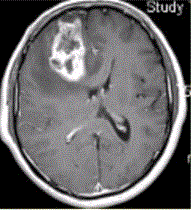

问题 患者女,67岁,头痛伴呕吐1周。既往体健。MR表现如下图。 多形性成胶质细胞瘤的转移途径不包括

选项 A.室管膜 B.淋巴转移 C.脑膜 D.血管周围间隙 E.也可转移至颅外

答案 B